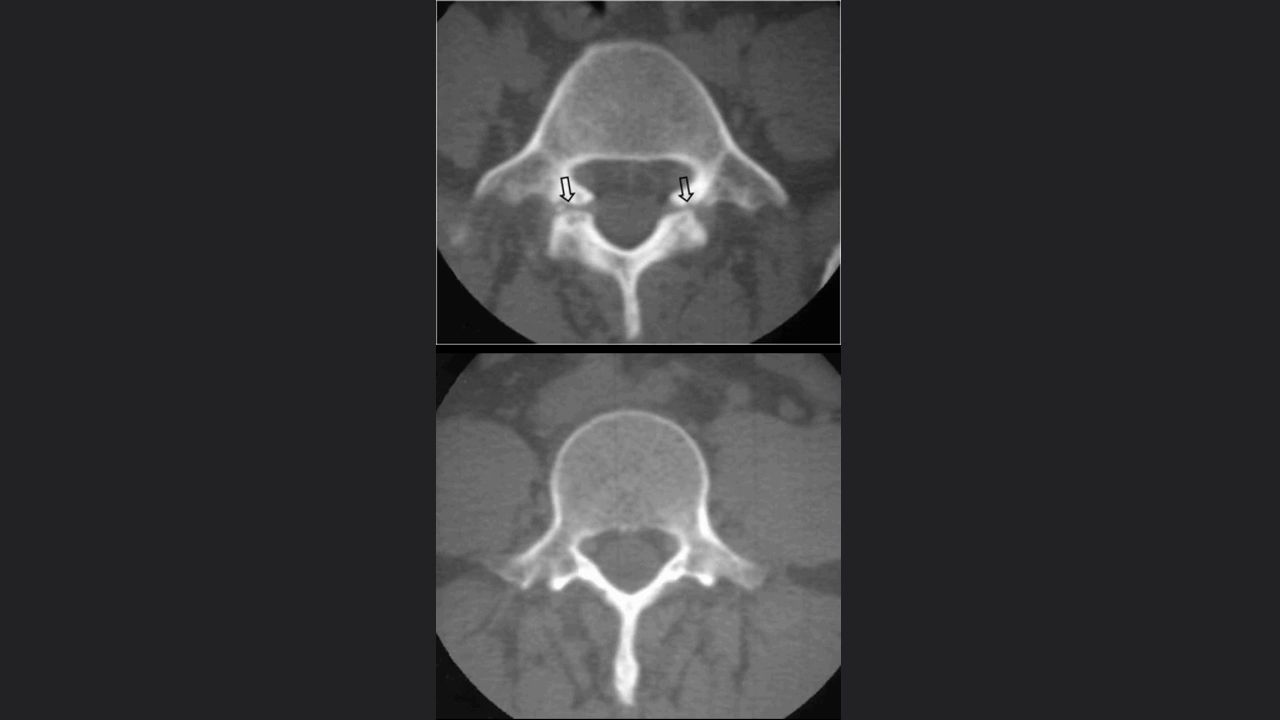

Espondilolisis

Espondilitis anquilosante

Columna traumática

Fracturas ligamentarias